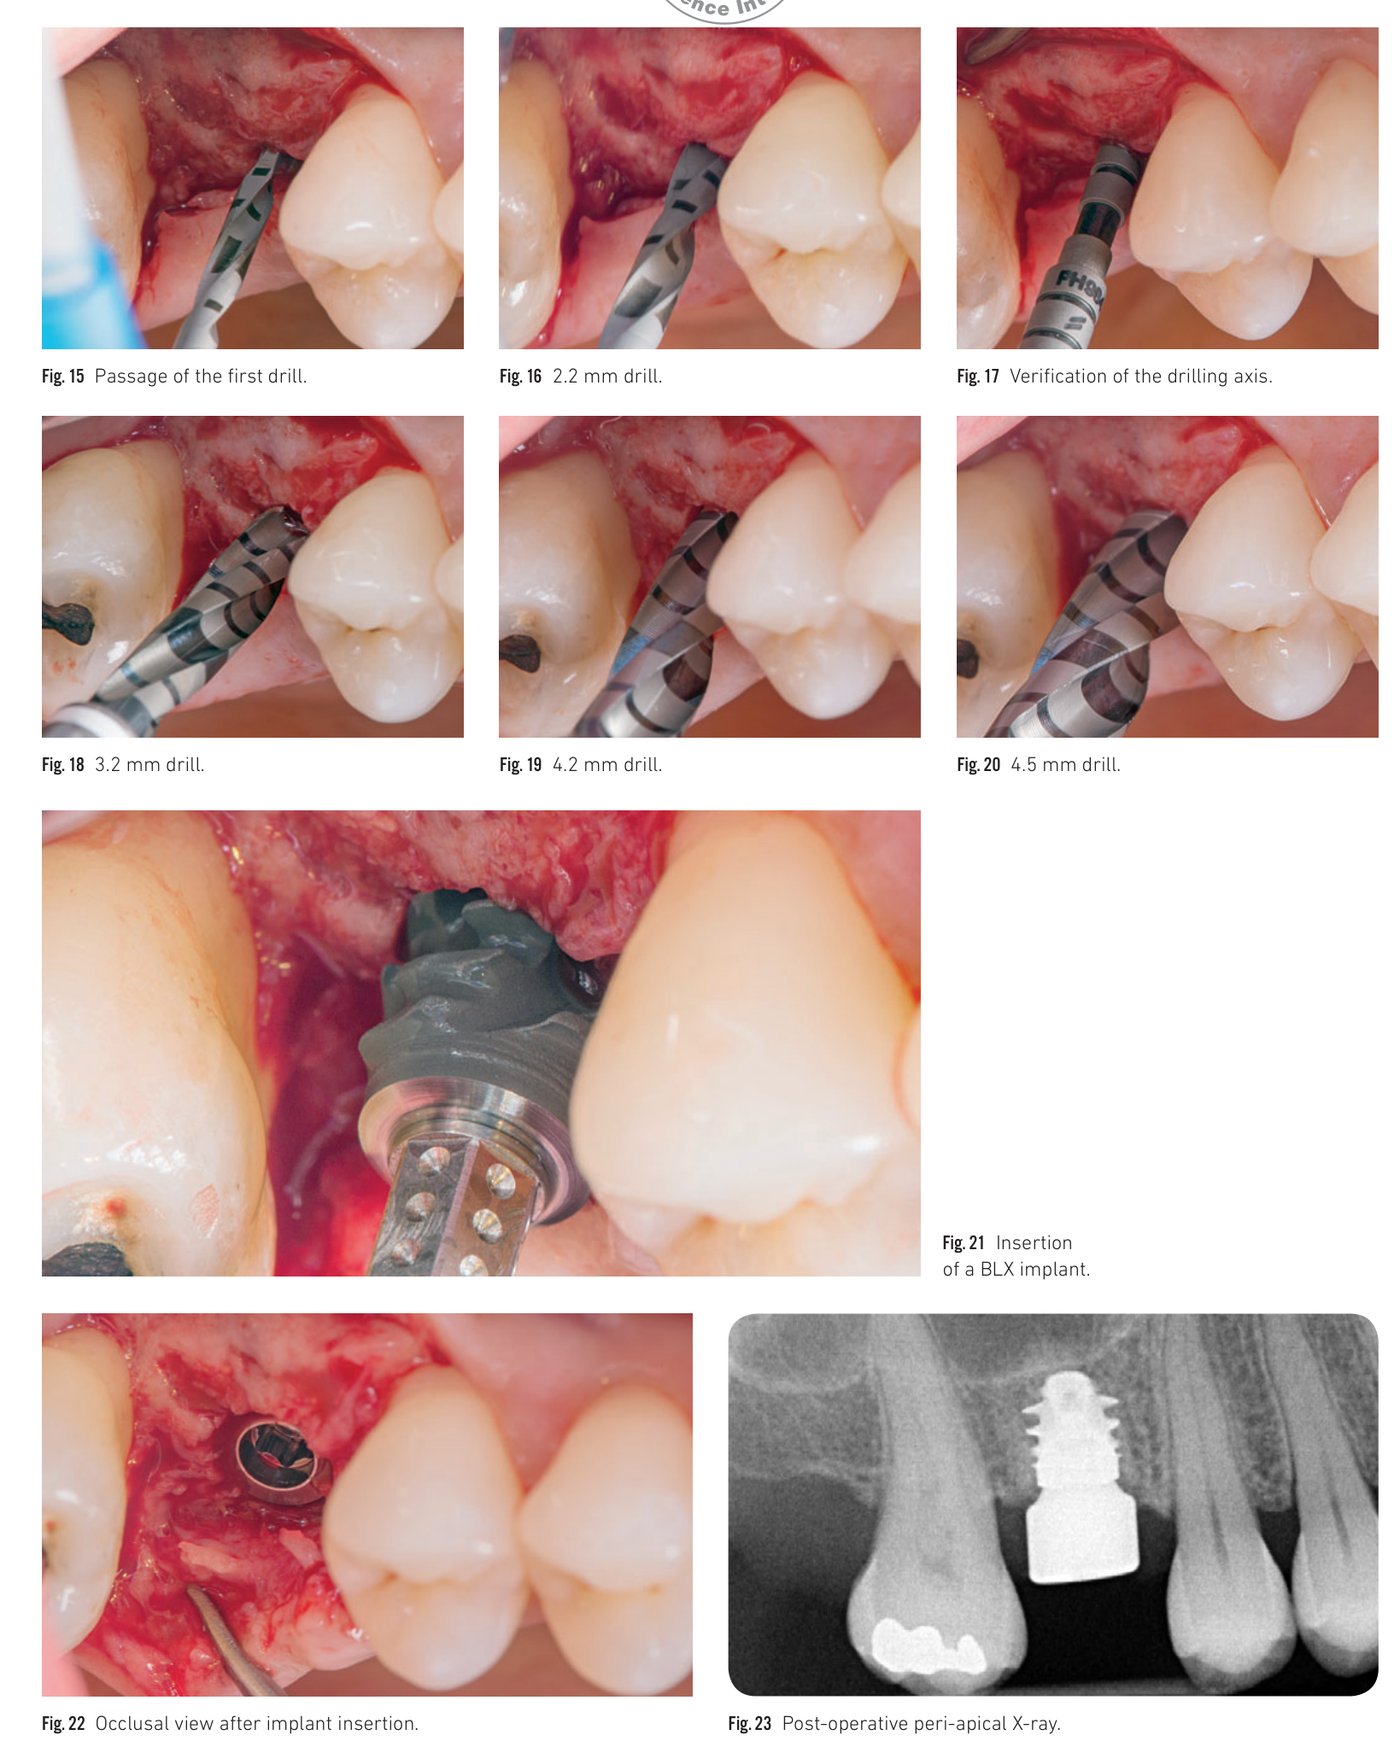

Surgical protocol demonstration: step-by-step from osteotomy preparation to implant seating (Fig 15-23)

Immediate implant placement in the posterior area

Since an early publication in 1989, immediate implant placement after single-rooted tooth extraction has become a regularly proposed procedure, since successfully extended to multirooted teeth. Cumulative survival rates for implants placed immediately after molar extraction are comparable to those placed in healed sites. The essential factor for success is initial implant stability via apical and/or lateral bone. At a molar extraction site, primary stability may be difficult to achieve due to socket size, poor bone quality, or anatomical limitations (maxillary sinus, mandibular canal). The specific design of the BLX allows satisfactory primary stability even in a very reduced septum.

Clinical situation 2, page 1: Preoperative view, atraumatic extraction, and BLX insertion

Clinical situation 2, page 2: Xenograft filling, collagen sponge, healing, and peri-apical X-ray